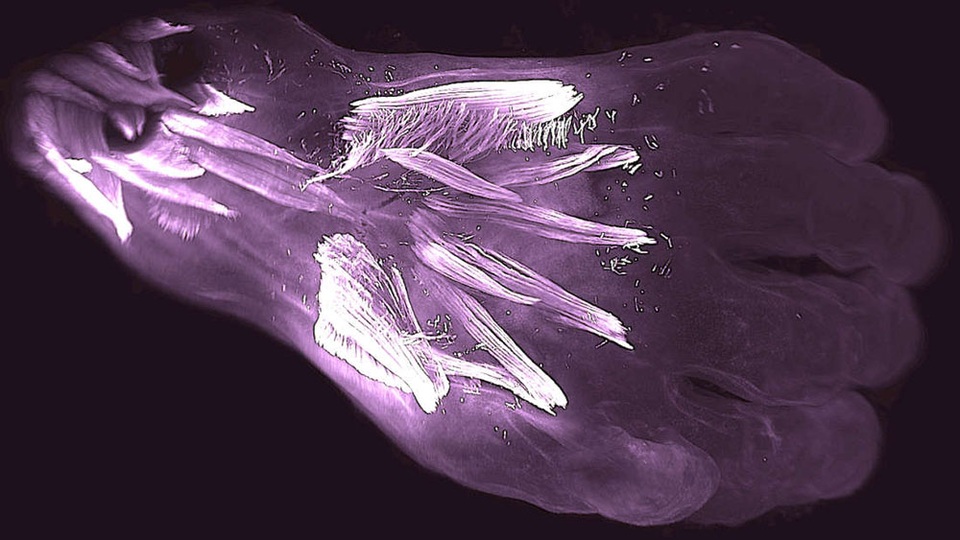

Nhóm nghiên cứu đã nắm bắt sự đặc biệt bằng cách sử dụng công nghệ mới tạo ra hình ảnh 3D có độ phân giải cao từ phôi và thai trong ba tháng đầu của thai kỳ.

Họ phát hiện ra rằng lúc 7 tuần tuổi thai (khi thai nhi có kích thước bằng quả việt quất), có khoảng 30 cơ trên tay. Vào tuần thứ 13 (kích thước của một quả chanh), 10 trong số chúng được hợp nhất và số lượng cơ bắp giảm xuống 20. Một số trong số chúng thậm chí biến mất trong quá trình chuyển từ các đặc điểm như bò sát sang động vật có vú.

Nhóm nghiên cứu cho biết đã có thể nắm bắt được thời gian biểu chi tiết về sự xuất hiện của các cơ này, cũng như sự phân tách, hợp nhất hoặc mất của chúng trong quá trình sinh trưởng và phát triển của phôi.

Các cơ bắp hợp nhất được gọi là cơ bắp chân tay, được hình thành trong quá trình phát triển ban đầu của con người. Nó cung cấp một cái nhìn thú vị về sự tiến hóa. Chúng ta thường thấy bản thân ngày càng phức tạp hơn, nhưng một số tính năng giải phẫu hợp lý hóa và trở nên đơn giản hơn.